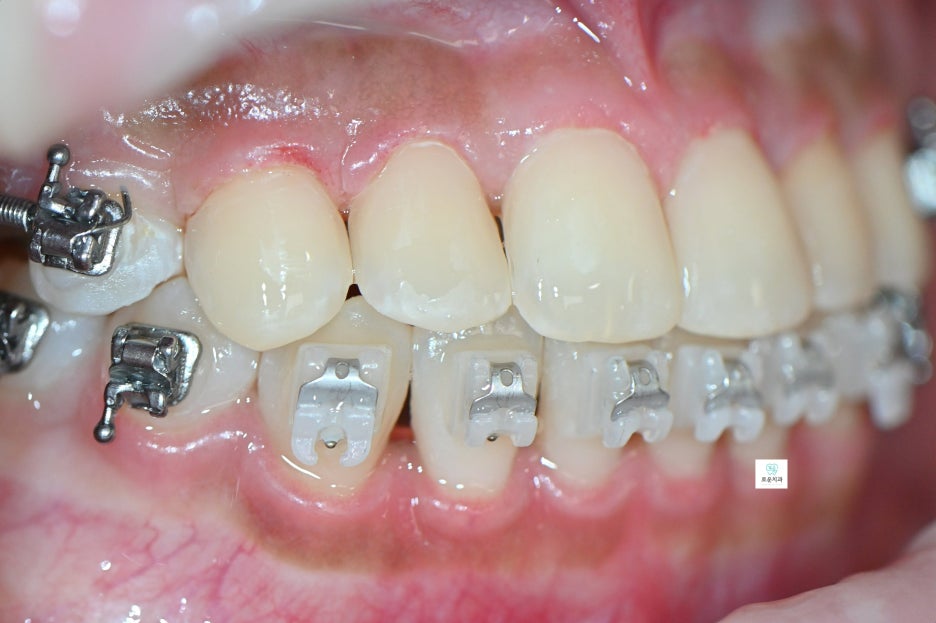

“교정 중 브라켓 주변 충치 치료 사례”

브라켓 주변에 여러 개의 충치가 발생하여

장치를 제거한 후 치료를 진행한 사례입니다.

한 치아 기준 약 3면 정도의 우식이 확인되어

충치 제거 후 수복 치료를 진행했습니다.

앞니 치료를 먼저 시행한 후

소구치와 대구치 부위 충치까지

순차적으로 치료를 완료했습니다.